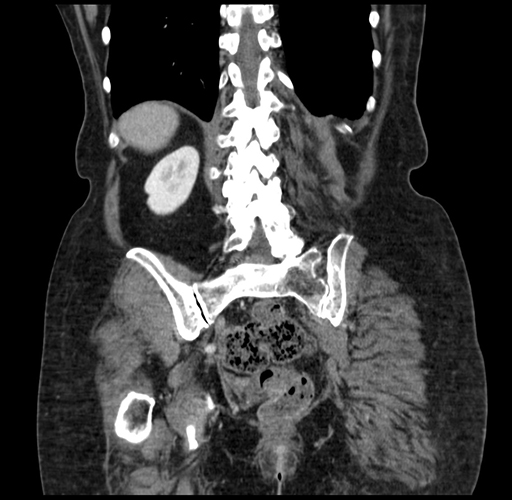

Pre-Chemo: Coronal Venous